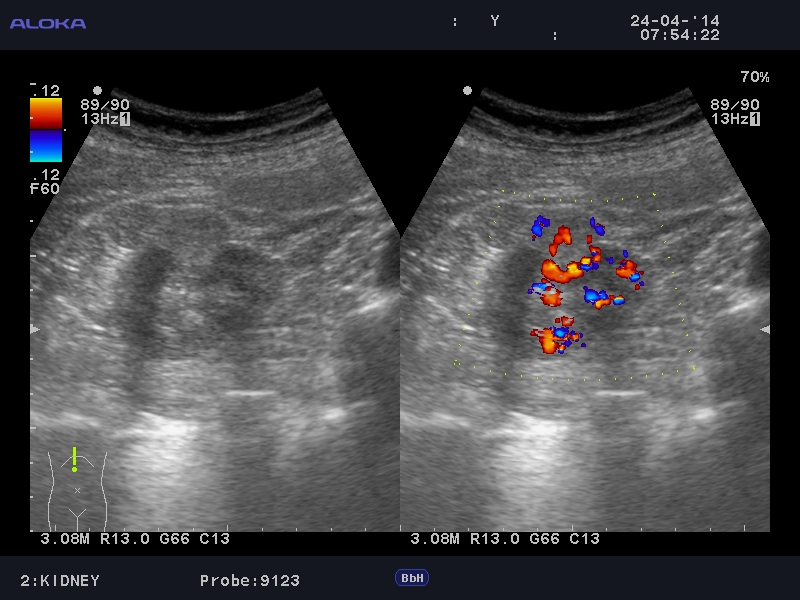

Онкоцитома почки - УЗИ

Женщина 76 лет. Жалоб не предъявляет.

Renal oncocytoma